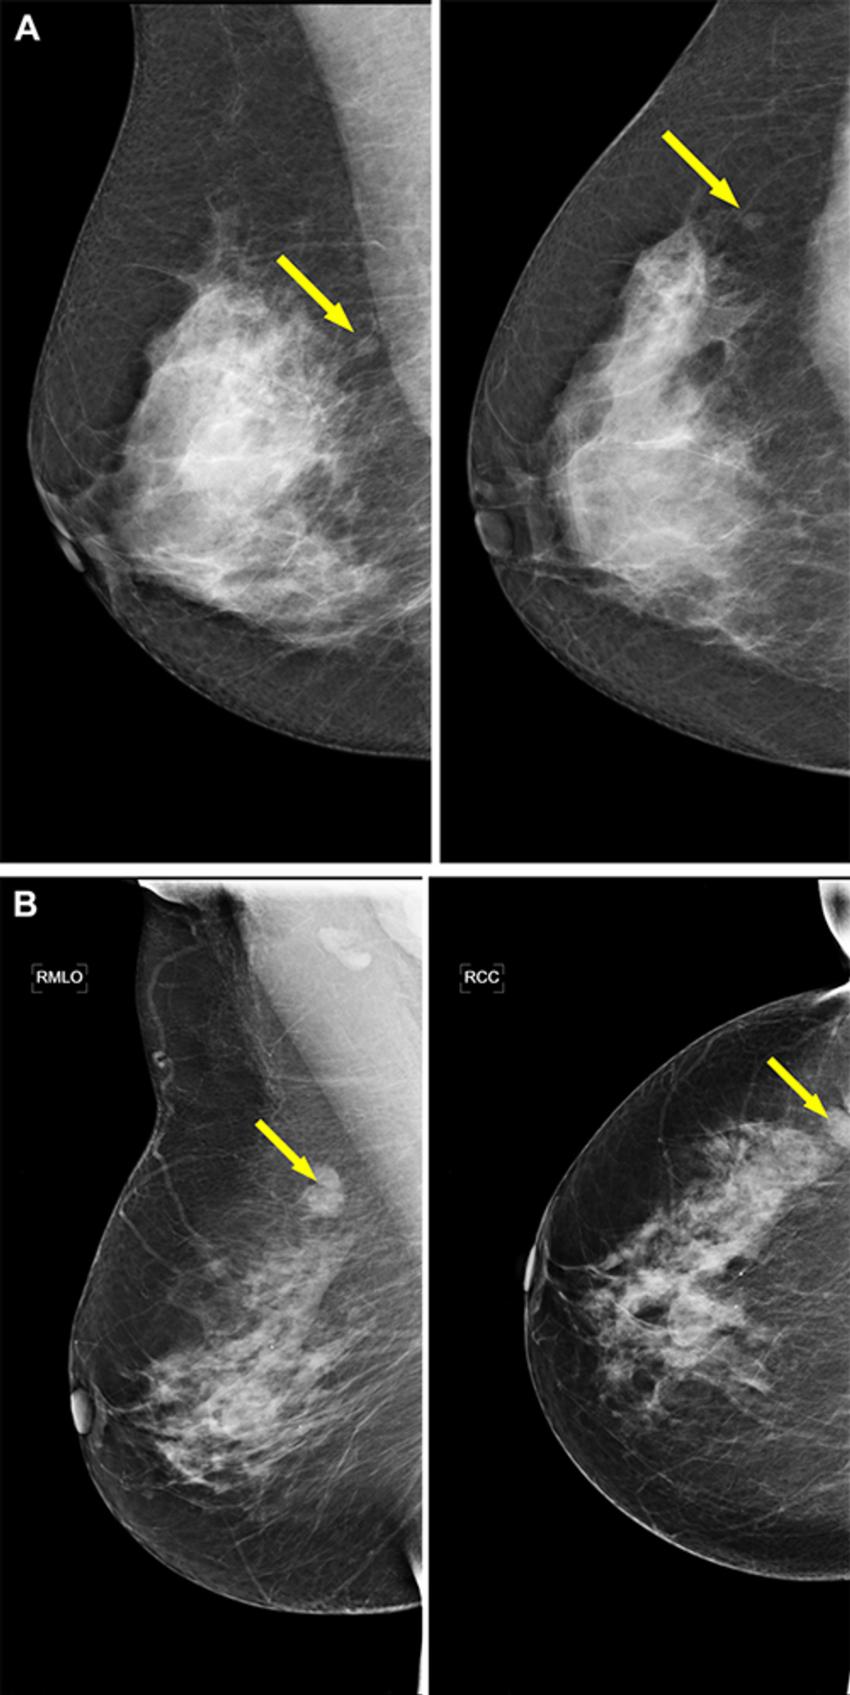

Figure 5. Example screening mammograms with an invasive ductal carcinoma (arrows) in which the women would not have been recalled with an AI–reading-only strategy. However, these examinations would have been shown to radiologists in a hybrid reading strategy based on the AI uncertainty score of the entropy of the mean probability of malignancy (PoM) score of the most suspicious region. For both examinations, mediolateral oblique (left) and craniocaudal (right) views of the affected breast are shown. (A) Images in a 67-year-old woman who was recalled because both radiologists scored the right breast as Breast Imaging Reporting and Data System (BI-RADS) 0. The woman would not have been recalled if the examination was read by the AI model, which assigned a PoM score of 40, but the prediction would have been classified as an uncertain prediction with an uncertainty quantification of 0.86. (B) Images in a 63-year-old woman who was recalled because both radiologists scored the right breast as BI-RADS 4. The woman would not have been recalled if the examination was read by the AI model, with a PoM score of 44, but the prediction would be classified as an uncertain prediction with an uncertainty quantification of 0.98.